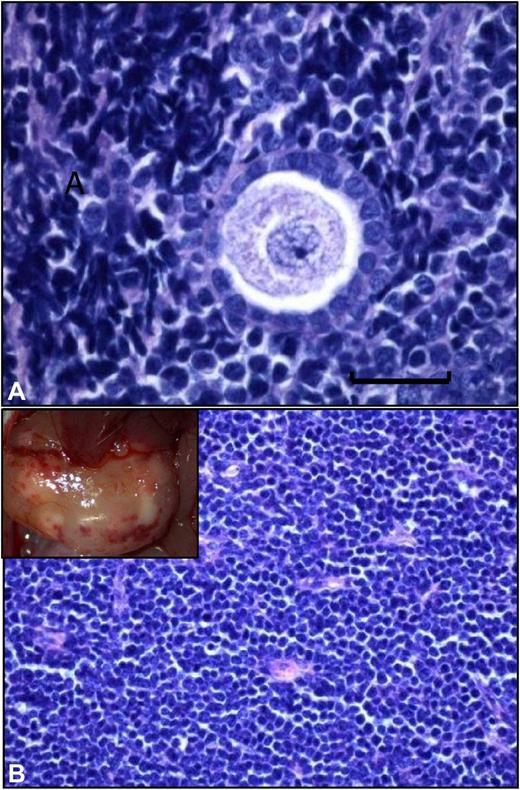

Grafted frozen-thawed ovarian tissue from a leukemia patient. (A) Histologic analysis of a frozen-thawed ovarian fragment from a leukemia patient recovered from a mouse after 6 months' xenografting. Normal ovarian stroma is no longer present, and a human follicle encircled by a large number of proliferating malignant lymphocytes can be seen (scale bar = 20 μm). (B) Large, white, burgeoning mass that corresponded to massive peritoneal invasion by leukemic cells.

We have previously reported that xenografting of cryopreserved ovarian tissue from leukemia patients (chronic and acute leukemia) resulted in development of leukemic tumors (see figure).4 Differences between the results of these 2 studies may be explained, at least partially, by the fact that of the 25 women Greve et al studied, 17 had received chemotherapy and were in remission, 4 had received initial treatment but had not achieved remission, 3 had chronic-phase chronic myeloid leukemia, and 1 had an unknown remission status at the time of ovarian biopsy and cryopreservation.1,4